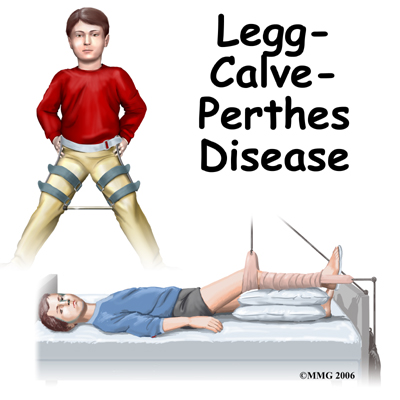

Perthes disease is a condition that affects the hip in children between the ages of four and eight. The condition is also referred to as Legg-Calve-Perthes disease in honor of the three physicians who each separately described the disease. In this condition, the blood supply to the growth center of the hip (the capital femoral epiphysis) is disturbed, causing the bone in this area to die. The blood supply eventually returns, and the bone heals. How the bone heals determines what problems the condition will cause in later life. Perthes disease may affect both hips. In fact, 10 to 12 percent of the time the condition is bilateral (meaning that it affects both hips). This condition can lead to serious problems in the hip joint later in life.

Perthes disease is a condition that affects the hip in children between the ages of four and eight. The condition is also referred to as Legg-Calve-Perthes disease in honor of the three physicians who each separately described the disease. In this condition, the blood supply to the growth center of the hip (the capital femoral epiphysis) is disturbed, causing the bone in this area to die. The blood supply eventually returns, and the bone heals. How the bone heals determines what problems the condition will cause in later life. Perthes disease may affect both hips. In fact, 10 to 12 percent of the time the condition is bilateral (meaning that it affects both hips). This condition can lead to serious problems in the hip joint later in life.

Many children who are diagnosed with Perthes disease do not require any treatment except careful watching. When the condition is mild, the results of not doing anything are often as good as aggressive treatment. The majority of children who are treated for Perthes disease these days require only a program for maintaining a near-normal range of motion. This may include nighttime splinting, home traction, and Chiropractic (see below.) The surgeon will determine treatment based on the classification of the severity of the disease. The classification is determined by the X-ray findings.

When lack of motion has become a problem, the child may be admitted to the hospital and placed in traction. Traction is used to give the joint some space and therefore quiet the inflammation. The rest for the joint while in traction also helps to settle the inflammation. Settling the inflammation usually takes about a week. Home traction may also be an option.

In the past, surgeons have tried to hold the hip in the best position where the femoral head was molded by the acetabulum using many different casts and braces. The most common way of doing this today is the Scottish Rite Orthosis. This brace fits around the waist and thighs and has hinges at the hip joints. The brace allows the child to walk and play while it holds the hip joint in the best position for containment. Your doctor may prescribe this for your child once they leave the hospital. Your Chiropractor will help your child learn to safely use crutches or a walker/frame if they are needed while in the brace.